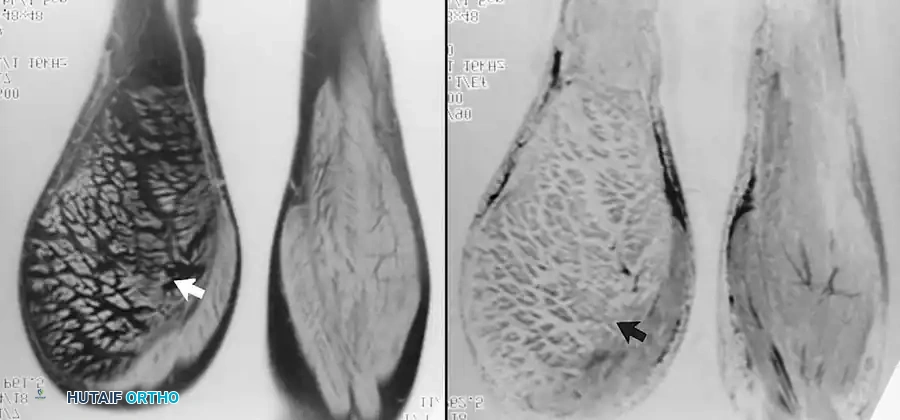

على صور الرنين المغناطيسي، يظهر التمزق الكامل كانقطاع مفاجئ في ألياف الوتر، وغالباً ما يكون مصحوباً بتراجع الوتر إلى الأعلى وتجمع للسوائل أو الدم حول منطقة الإصابة.

صورة رنين مغناطيسي توضح تمزق وتر العضلة ذات الرأسين البعيد وتراجعه

تمزق الوتر المثني العميق للأصابع وتراجعه داخل اليد